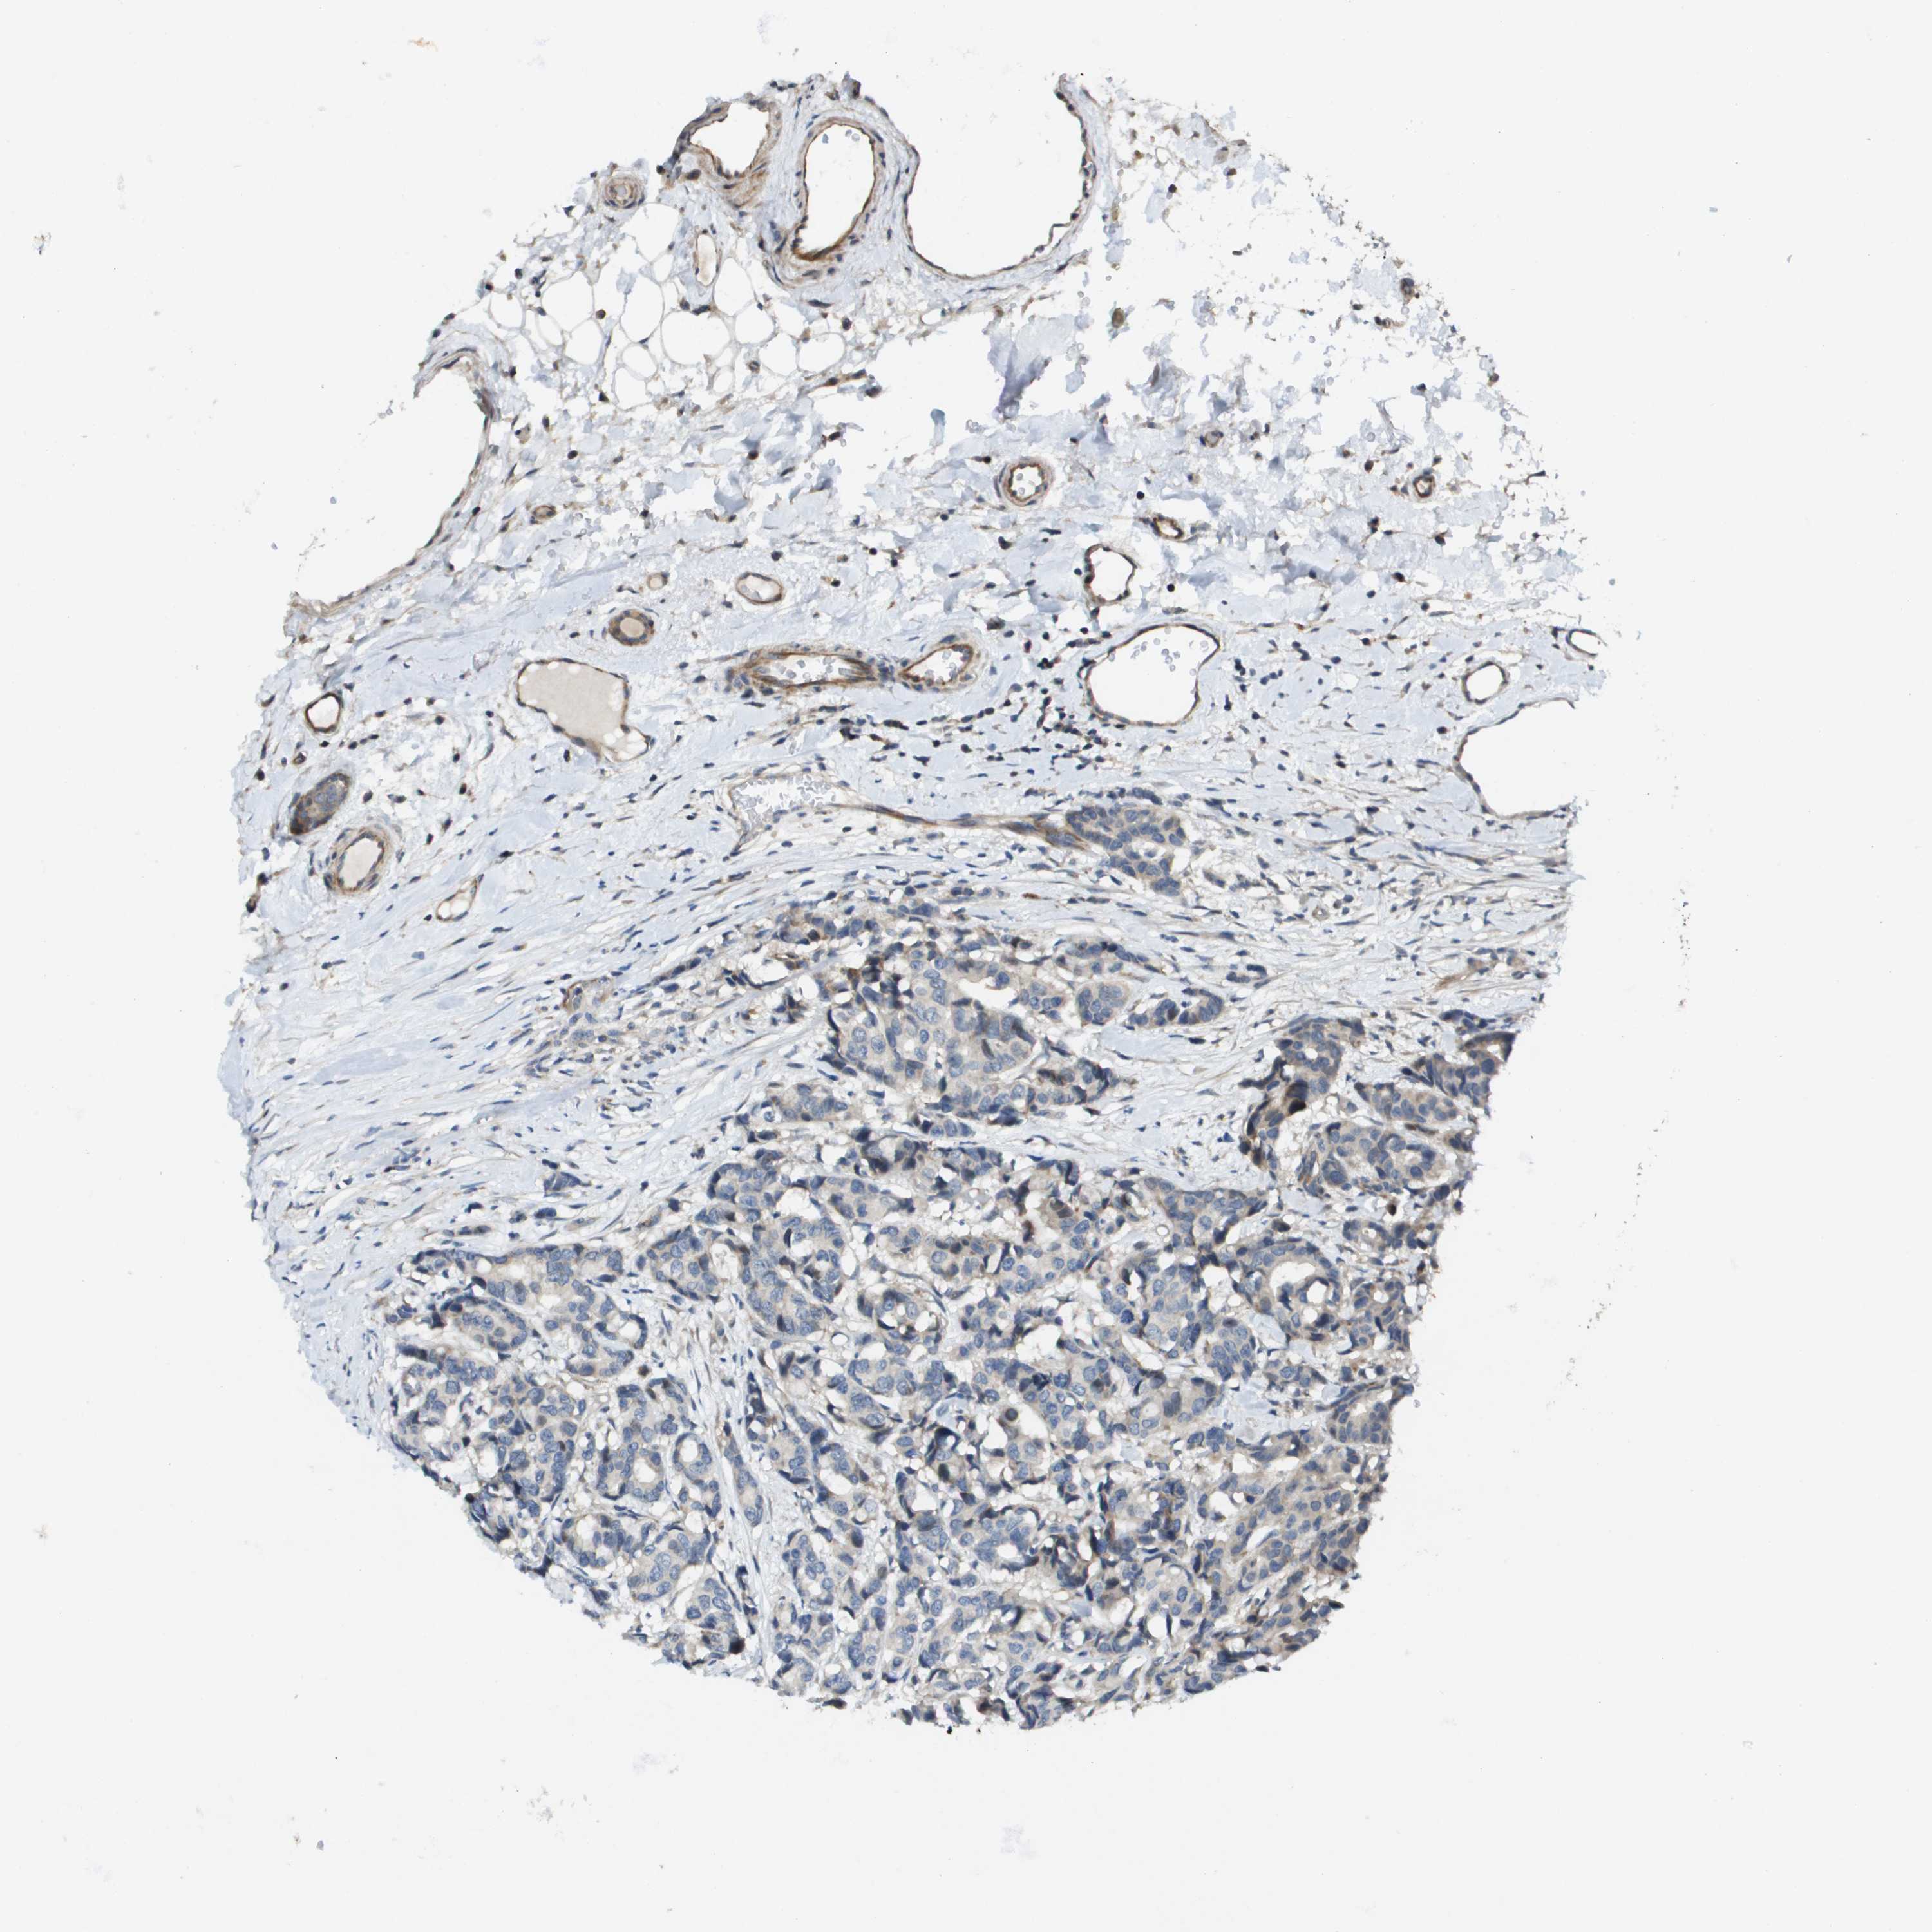

BRCA TCGA BRCA VALIDATION PROTEIN EXPRESSION

ANTIBODIES

AND

VALIDATION